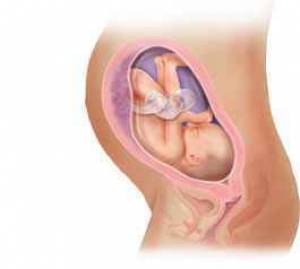

بارداری هفته به هفته و تغییر وضعیت جنین+عکس

بارداری معمولا 280 روز یا 40 هفته بطول می انجامد، که بطور قراردادی از اولین روز آخرین قاعدگی شروع می شود. این دوران را می توان به سه "سه ماهه" بارداری تقسیم کرد که در هر یک وقایع خاصی اتفاق می افتد؛ سه ماهه اول از اولین هفته بارداری تا انتهای هفته 13، سه ماهه دوم از هفته 14 تا پایان هفته 27، و سه ماهه سوم از هفته 28 تا آخر هفته 40 است که عمدتا در این زمان (کمی زودتر یا دیرتر) به زایمان و تولد نوزاد ختم می شود.

هر سه ماهه مشخصات مربوط به خود را دارد؛ در سه ماهه اول ضربان قلب جنین شنیده می شود، در سه ماهه دوم اولین حرکات جنین توسط مادر احساس می شود، و در سه ماهه آخر برخی از مادران انقباضات کاذب زایمانی موسوم به برکستون- هیکز را تجربه می کنند. بعضی از آزمایشات مانند نمونه برداری از پرزهای جفتی در سه ماهه اول و آمنیوسنتز در سه ماهه دوم انجام می شوند. برخی از مسائل مانند دیابت بارداری، در سه ماهه آخر تظاهر می کنند. در این دوران عواطف و احساسات شما نیز مانند بدنتان دستخوش تغییراتی می شود و شرایط زندگی برای خانواده بتدریج آماده پذیرایی از کودک آینده خواهد شد.